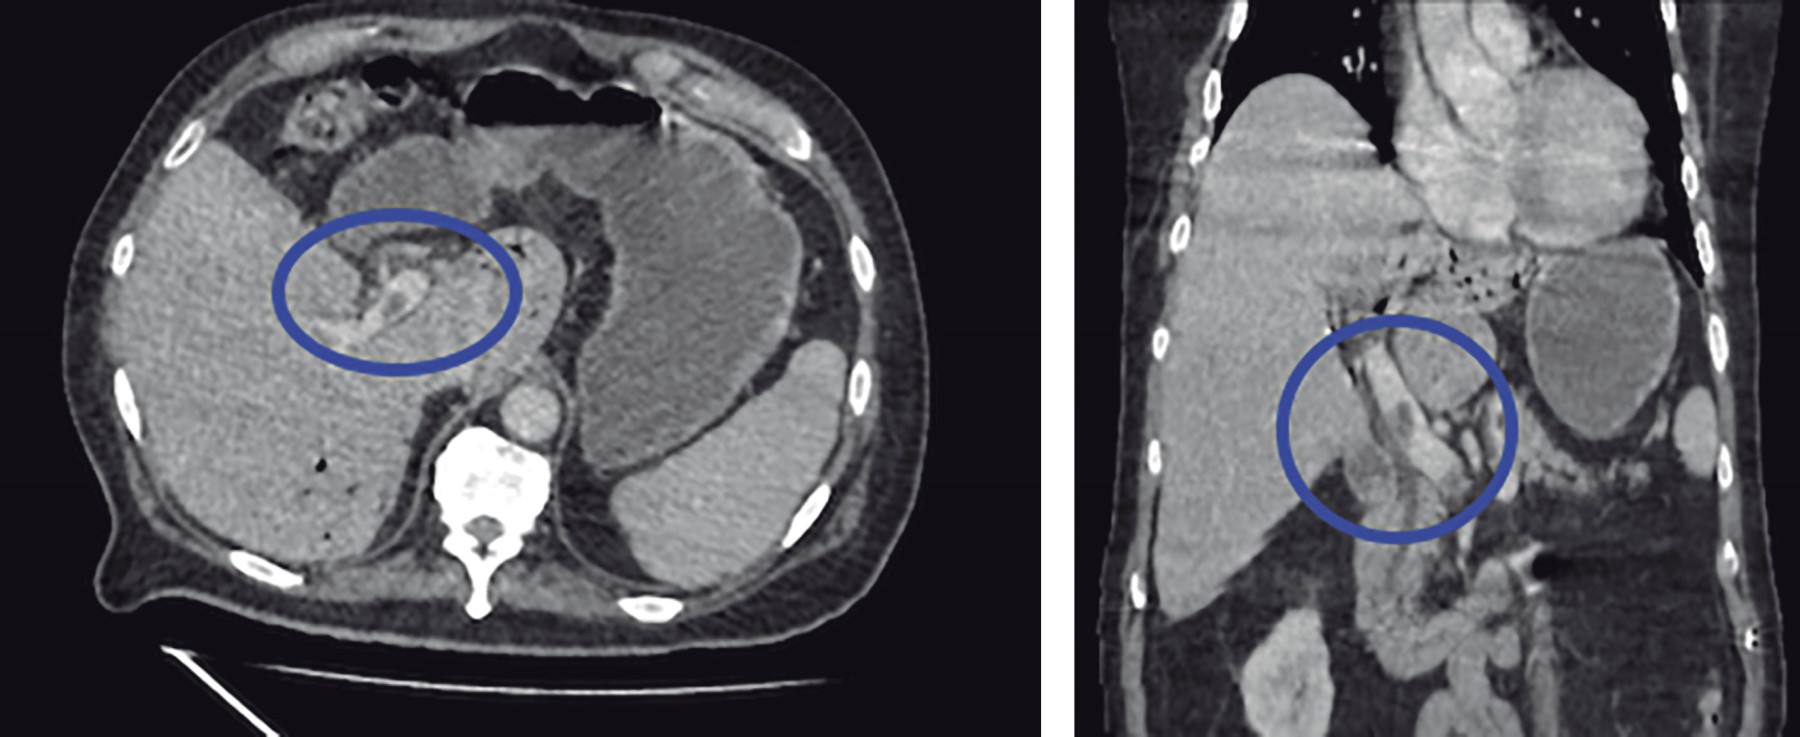

Masculino de 77 años con antecedentes de diabetes mellitus 2 e hipertensión arterial sistémica de larga evolución, antecedentes quirúrgicos de colecistectomía laparoscópica hace seis años y cateterismo cardiaco por cardiopatía isquémica crónica. Inicia su padecimiento actual 10 días previos a su ingreso con cuadro de dolor abdominal difuso en cuadrantes inferiores, así como ataque al estado general acompañado de astenia e hiporexia. Fue manejado por facultativo externo con antibioticoterapia. A su llegada al Servicio de Urgencias se presenta con taquicardia y tendencia a la hipotensión acompañado de alteración del estado de alerta. A la exploración física se palpa plastrón inflamatorio en cuadrante inferior izquierdo que despierta dolor a la manipulación del mismo, sin embargo, no hay datos de irritación peritoneal, sus laboratoriales con leucocitos 13,400 mm3, neutrofilia 92.9% y lactato de 3.9 mmol/l. Se solicita tomografía abdominopélvica contrastada en donde se muestra trombosis de la vena porta (Figura 1), neumatosis portal (Figura 2) y enfermedad diverticular (Figura 3), por los hallazgos anteriores se da manejo inicial con soluciones intravenosas y antibioticoterapia empírica de amplio espectro con piperacilina-tazobactam 4.5 g IV cada 8 horas, posterior al manejo estabilizador se realiza laparotomía exploradora, en donde se realiza sigmoidectomía y colostomía terminal debido a los hallazgos de perforación diverticular (Figuras 4 y 5) y plastrón inflamatorio purulento en el mesosigmoides con especial distribución en el trayecto de la vena mesentérica inferior, se toma cultivo y se maneja el posoperatorio en terapia intensiva, se deja antibioticoterapia dirigida a E. coli. Se calcula nutrición parenteral total y se inicia terapia anticoagulante con enoxaparina 60 mg subcutáneos (SC) cada 12 horas. El paciente cursó con evolución clínica favorable gracias al manejo multidisciplinario que se brindó. Egresó a la semana del procedimiento quirúrgico sin complicación alguna, se cita a consulta externa una semana después de su egreso tolerando vía oral con estoma funcional y con la herida afrontada. El reporte de histopatología reveló enfermedad diverticular complicada.

Figura 1

Figura 2